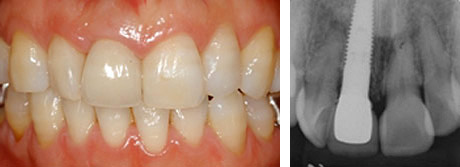

After

治療後:天然歯と見分けがつかないぐらいに治っています。